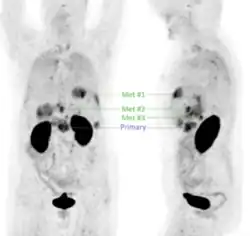

First-in-human application of different αvβ6-integrin radiotracers has demonstrated that 68Ga-Trivehexin performed especially well in detecting pancreatic cancer, showing high uptake in tumor lesions and low background in the gastrointestinal tract (GI tract) (see image).[30] Since its introduction,[1] 68Ga-Trivehexin has been used predominantly for PET/CT imaging of pancreatic ductal adenocarcinoma (PDAC), for example, in single cases [28][31] and two cohorts (12 and 44 patients, respectively) [32][29] of suspected or known PDAC.

In a cohort of 20 suspected (19 confirmed) head-and-neck squamous cell carcinoma (HNSCC) cases, 68Ga-Trivehexin PET had a higher sensitivity (92.5%), positive predictive value (PPV, 100%), and accuracy (93%) than the standard 18F-FDG PET, for which sensitivity, PPV, and accuracy were 90%, 93.1%, and 84.3%, respectively.[32] 68Ga-Trivehexin was furthermore applied in a case of tonsillar carcinoma metastasized to the brain (see image).[31]